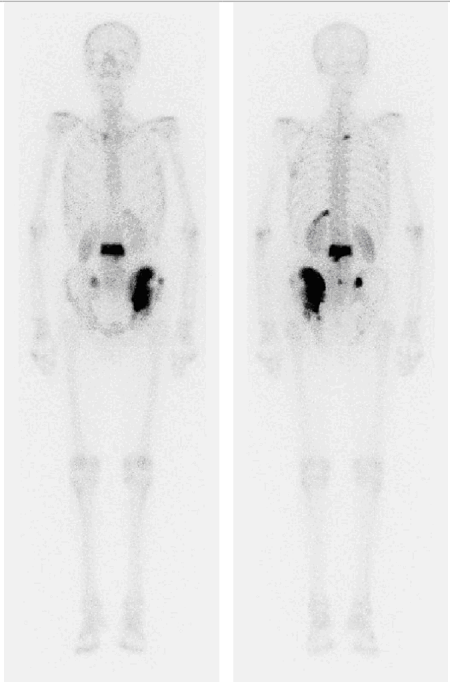

Vyšetření jsme provedli za 2 hodiny po i. v. aplikaci 700 MBq 99mTc oxidronátu (přípravek TechneScan HDP) na dvouhlavé scintilační tomografické kameře E.CAM opatřené kolimátory LEHR. Scintigramy v přední a zadní projekci byly střádány současně po dobu 15 minut (obr. 1).

Obr. č. 1 – Celotělové scintigrafie skeletu v přední a zadní projekci

Jsou patrná patologická ložiska výrazně zvýšené osteoblastické aktivity v obratli L3, v lopatě levé kosti kyčelní zasahující do levého SI skloubení. Oproti předchozím scintigramům jsou nová dvě ložiska ve 12. vlevo. Jedná se o vícečetné kostní metastázy.